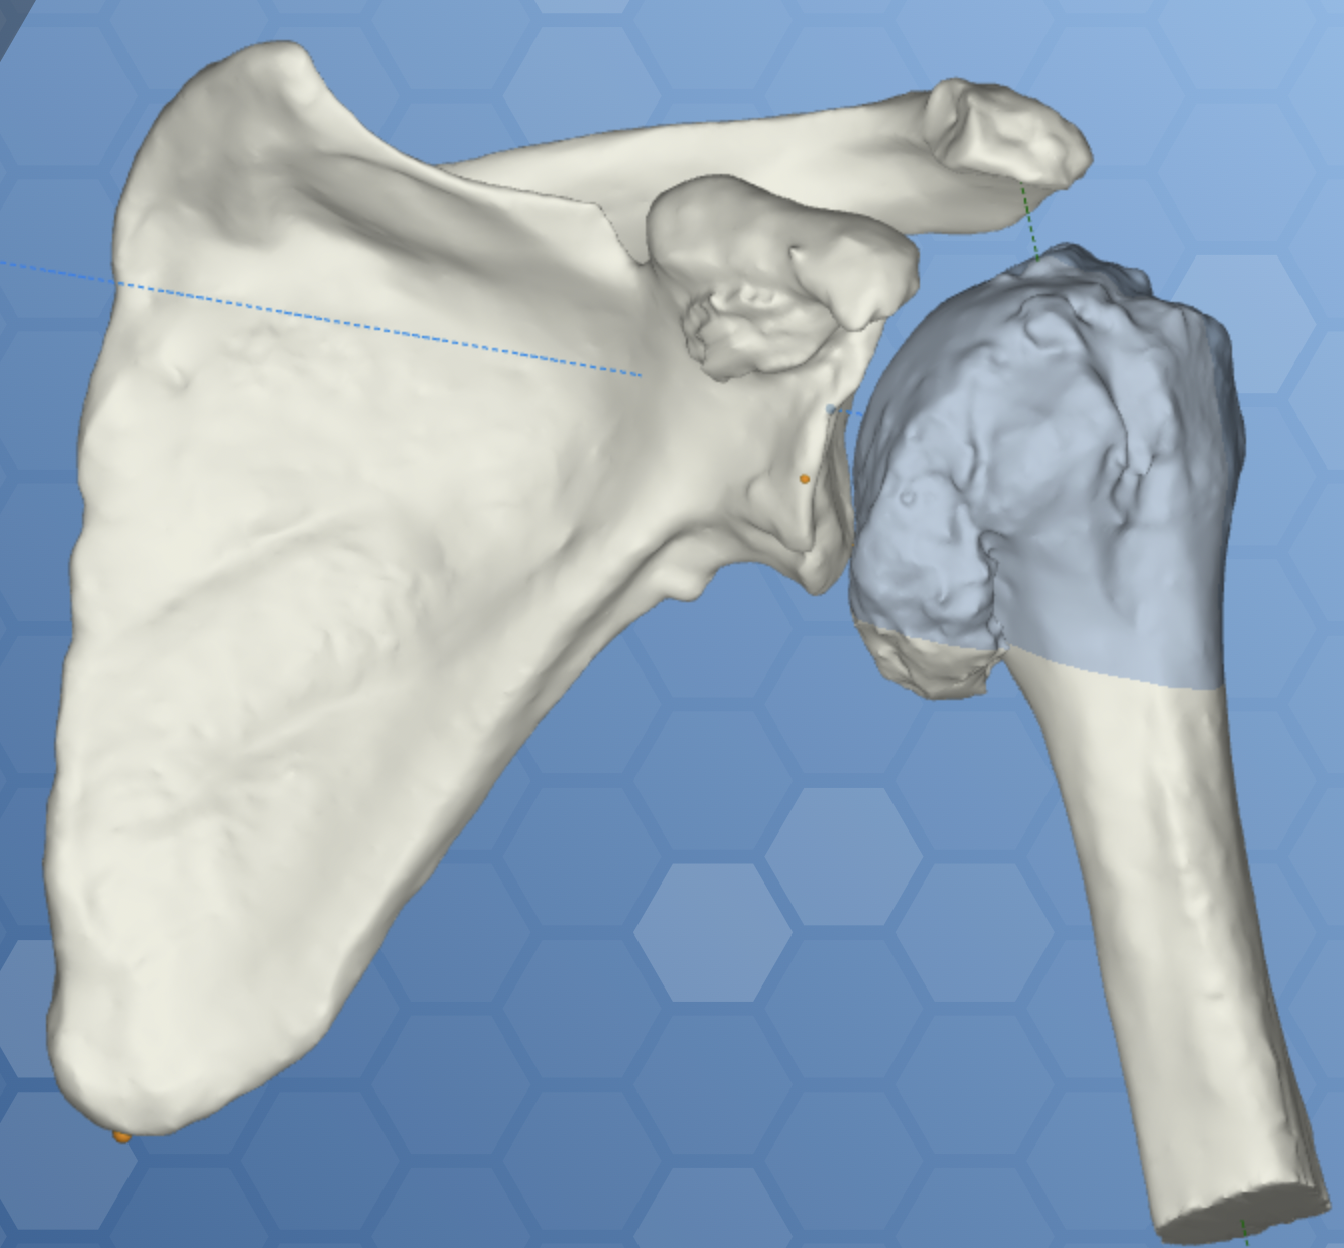

Obecnie istnieją programy komputerowe, które ułatwiają planowanie zabiegów operacyjnych. Procedura ta obejmuje przeprowadzenie tomografii komputerowej chorego stawu ramieniowego przed zabiegiem. Następnie wyniki badania są importowane do specjalnego oprogramowania, które generuje trójwymiarowy model operowanego stawu. Programy te oferują zestaw narzędzi, które umożliwiają precyzyjne zaplanowanie pozycji implantów oraz ich rozmiarów. W znacznym stopniu ułatwiają one przeprowadzenie zabiegu operacyjnego oraz zmniejszają ryzyko popełnienia błędu.